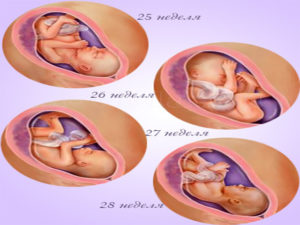

25 недель беременности: Как выглядит будущий малыш